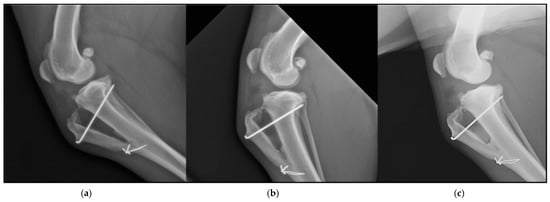

Figure 5.

Different times of ossification in a dog. (a) Ossification in the first follow-up. (b) Ossification in the second follow-up. (c) Ossification in the third follow-up.

The mean values for ossification degrees at follow-ups were 1.33 ± 1.13, 2.61 ± 0.84, and 3.55 ± 0.51, respectively. The ossification degrees presented statistically significant differences between each other (p < 0.05) when comparing the results between 1st and 2nd follow-ups, 1st and 3rd follow-ups, and 2nd and 3rd follow-ups (Table 2).